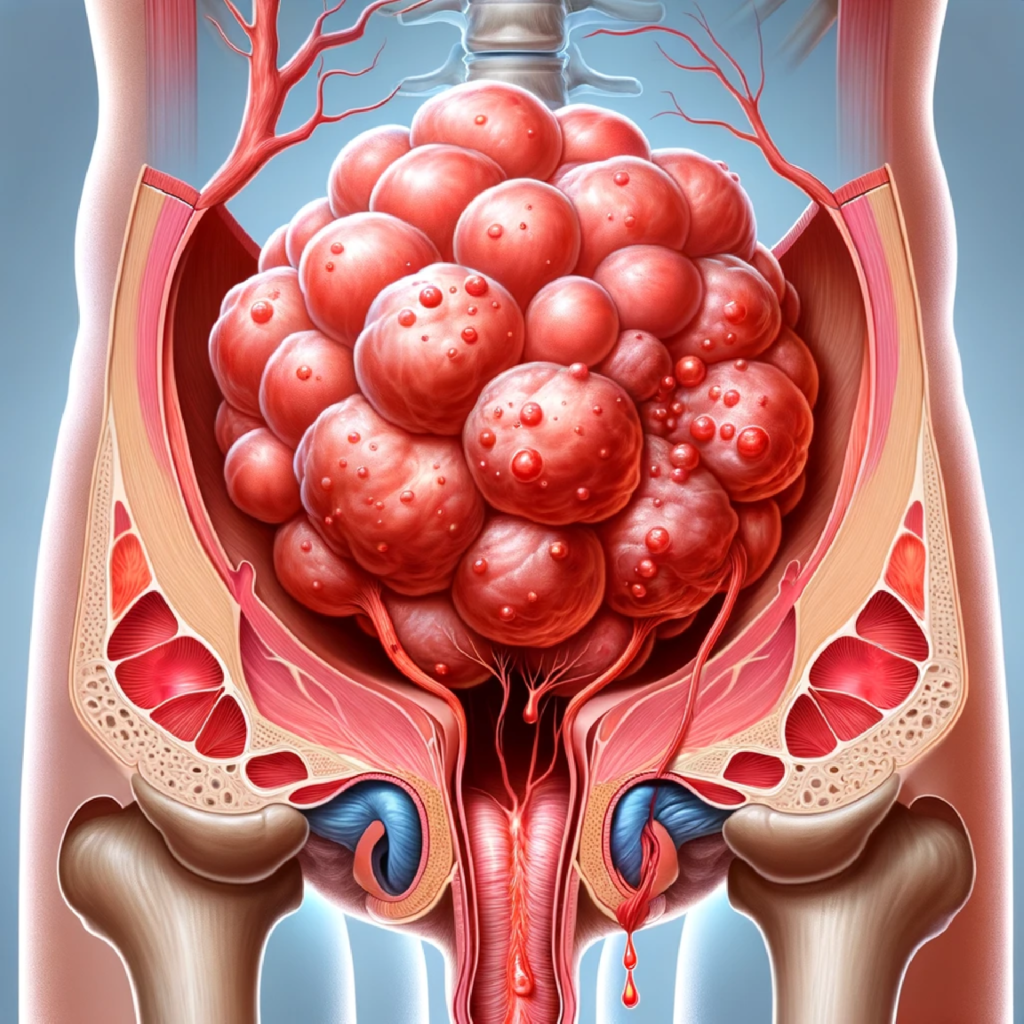

Kolon xərçənginin əsas səbəbləri arasında genetik amillər, qeyri-sağlam qidalanma alışkanlıqları, aş ...

Hemoroid: Təsvir: Anus ətrafındakı damarlarda şişlik və iltihab. Simptomlar: qanaxma, qaşınma, a ...

Ülseratif kolit: Tərif: Xoralı kolit yoğun bağırsaqda (kolon) iltihab və xoralarla xarakterizə ol ...